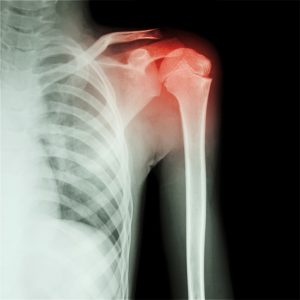

Shoulder examination

The shoulder and rotator cuff are examined: we will assess the rotator cuff tendons: (the biceps tendon and sheath, subscapularis, supraspinatus and infraspinatus tendon),  bursa and any soft-tissue swellings. The rotator cuff holds the shoulder joint together. Problems with the rotator cuff tendons can be the cause of many shoulder problems, which are becoming increasingly common due to the stress and strains.

Shoulder scan £165